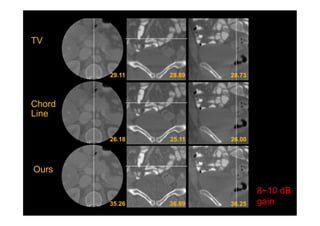

Deep Learning Interior Tomography

Han et al, arXiv preprint arXiv:1712.10248, (2017): CT meeting 2018.

Ground

Truth

FBP

TV

Chord

Line

Ours

8~10 dB

gain

Deep Learning InteriorTomography Han et al, arXiv preprint arXiv:1712.10248, (2017): CT meeting 2018.